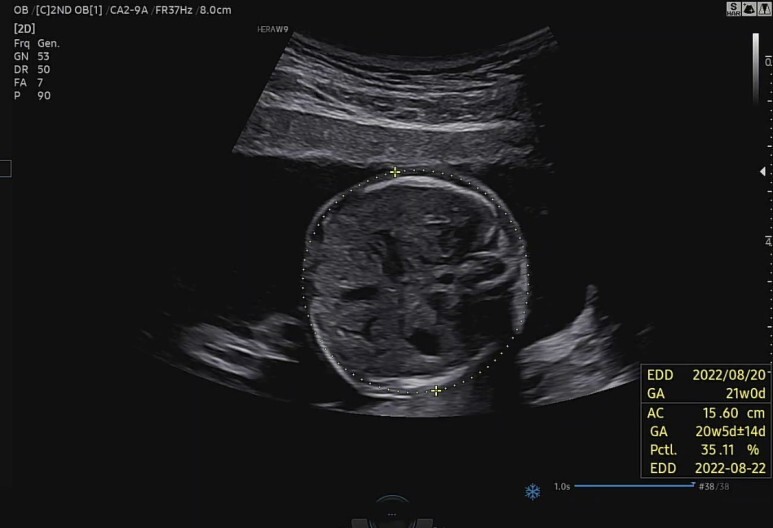

배둘레 확인(AC)